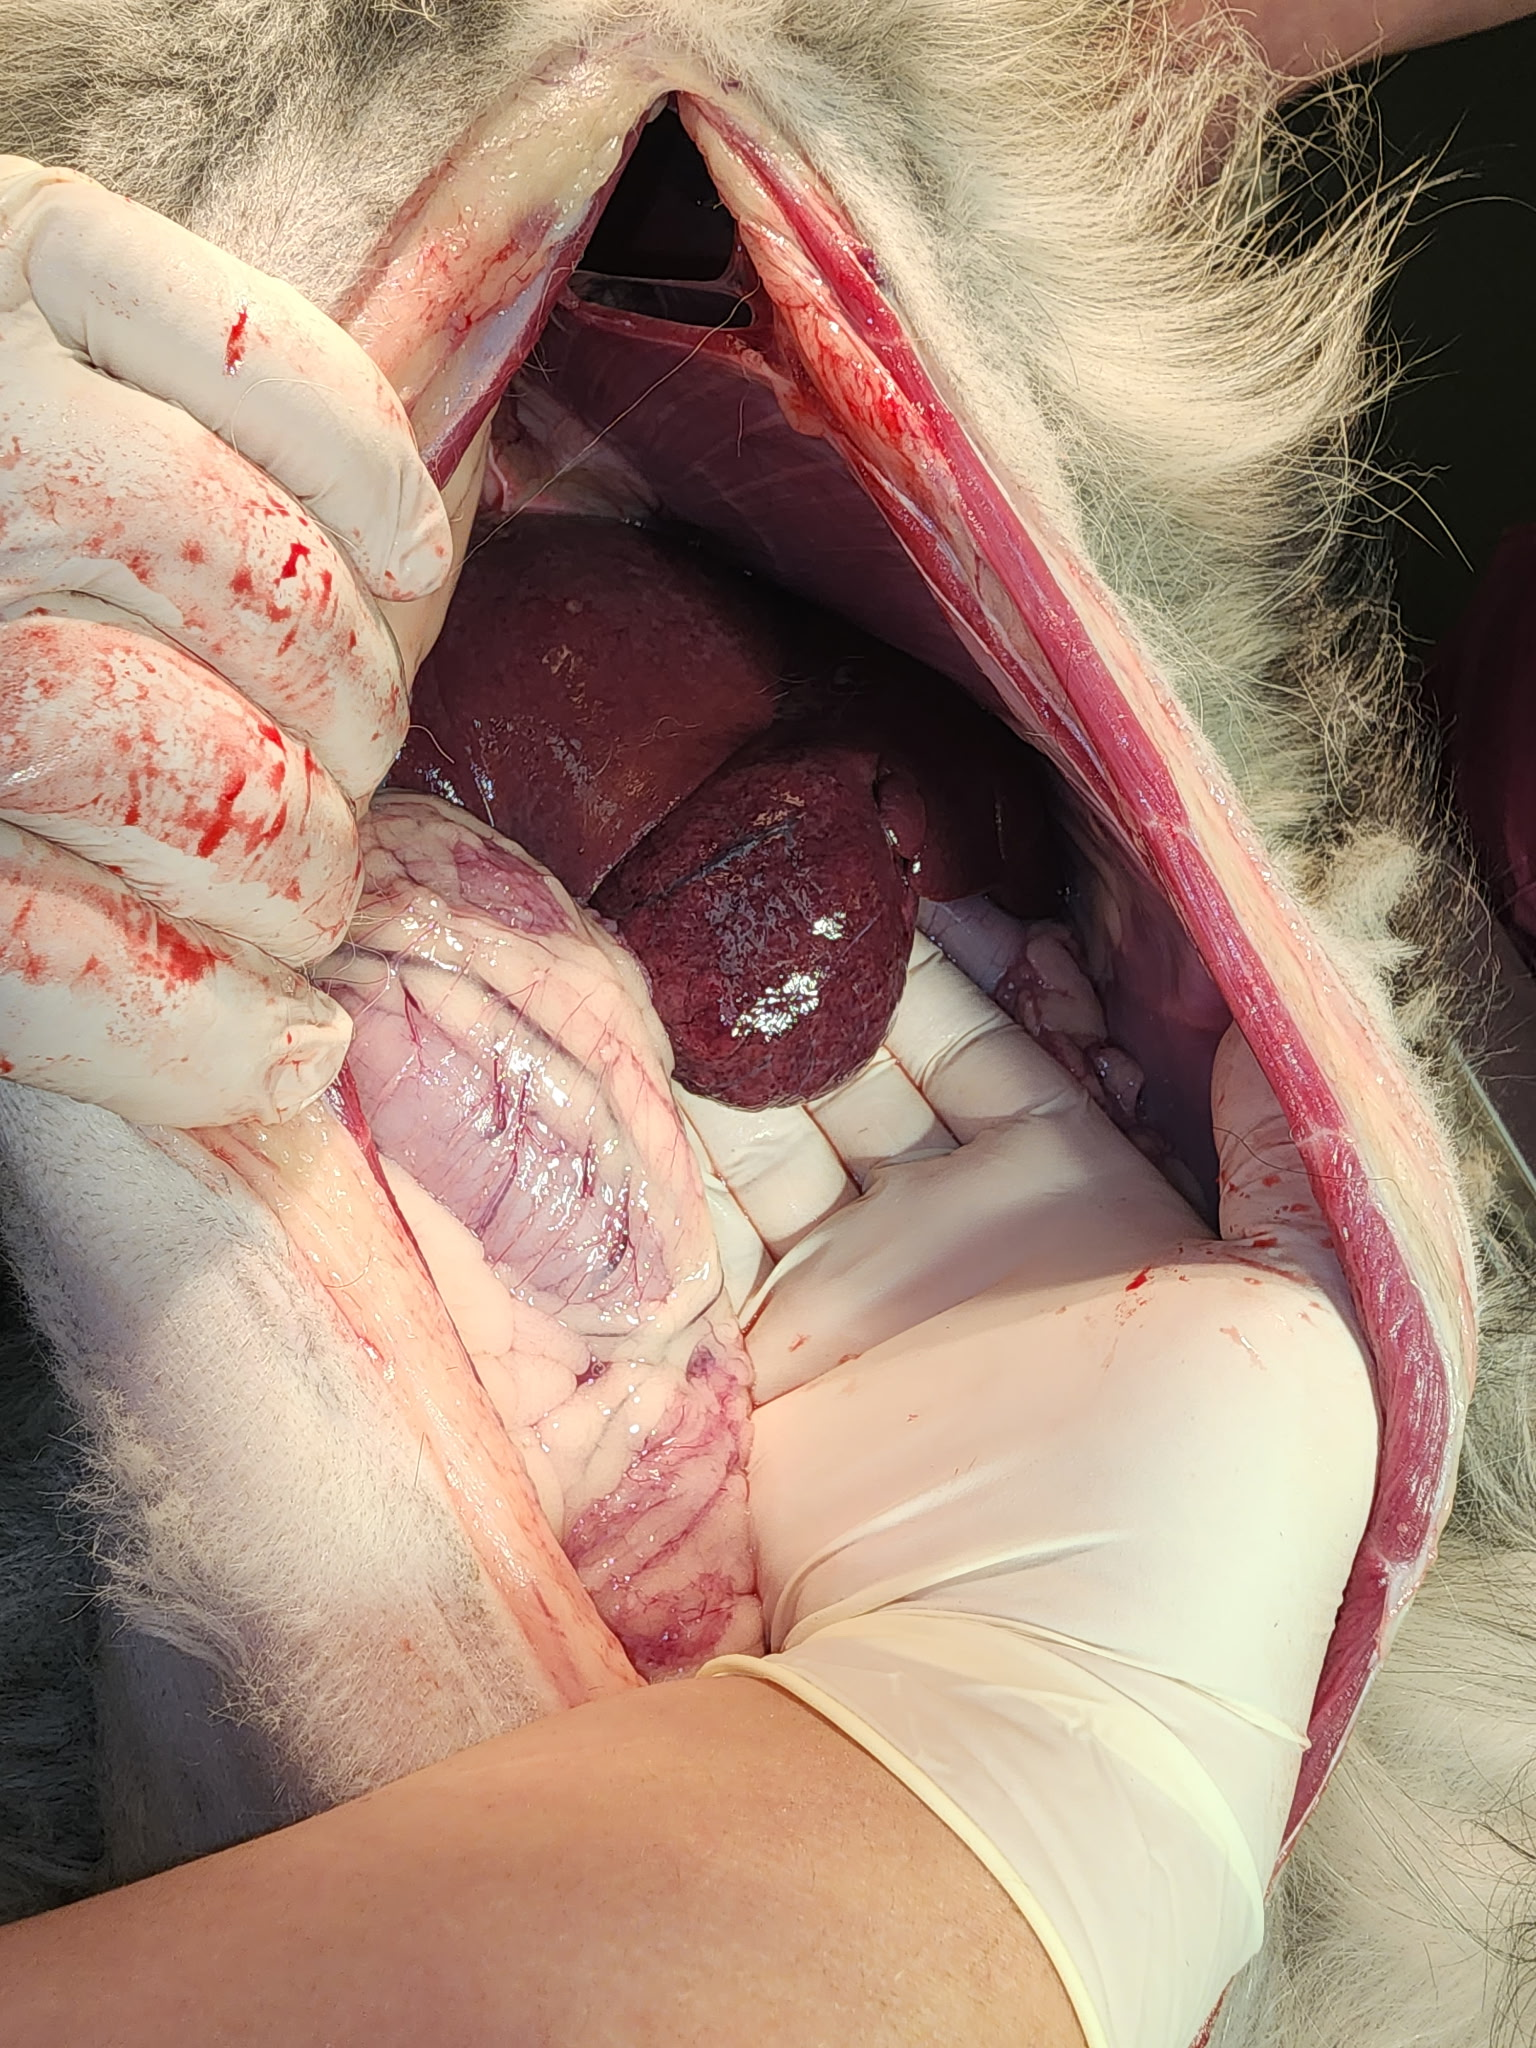

Image 2: Rounded mass on the left medial liver found on necropsy.

The owner elected humane euthanasia due to poor prognosis. Necropsy was performed.

A rounded liver mass was found on the medial left liver lobe. TNTC small pale nodules were found throughout the mesentery and pleural cavity. There was also a small amount of serosanguinous peritoneal fluid present.